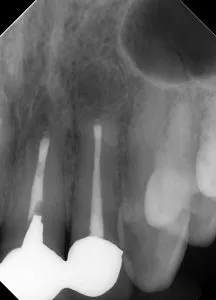

| 術前(写真) | 術後(写真) |

|---|---|

![]()

|

| 術名 | 歯根端切除術(逆根管治療) |

| 年齢 | 50代 |

| 性別 | 女性 |

| 主訴 | 前歯の根元の歯ぐきが痛い。現在の被せ物を外さずに治療したい。 |

| 診断名 | 根尖性歯周炎(右上2番、左上1番、左上2番の計3本) |

| 治療内容 | マイクロスコープ下での歯根端切除および逆根管充填(Lid Technique:BCシーラーとパテを使用) |

| 治療期間 | 約1年(手術自体は1日、その後経過観察) |

| 通院回数 | 手術は1回(その他、抜糸や経過観察の来院あり) |

| 費用 | 前歯1本あたり ¥143,000※手術単独で行う場合 |

| リスク・副作用 | 外科手術を伴うため、術後の腫れや痛み、内出血が起こる可能性があります。また、解剖学的な理由や病変の広がりによっては、完全な治癒に至らず抜歯が必要になる場合があります。 |

| 補足事項 | 【治療の選択理由】 患者様が「自費で作製した被せ物を外したくない」「治療回数を少なくしたい」という希望を持たれていたため、再根管治療ではなく外科的アプローチ(歯根端切除術)が選択されました。 【経過】 術後1年で3本とも根尖部の骨再生が完全に確認され、痛みなどの臨床症状も消失しました。 |